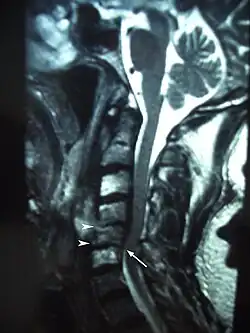

Osteoradionecrosis (ORN) is a serious complication of radiation therapy in cancer treatment where radiated bone becomes necrotic and exposed.[1] ORN occurs most commonly in the mouth during the treatment of head and neck cancer, and can arise over 5 years after radiation.[2] Common signs and symptoms include pain, difficulty chewing, trismus, mouth-to-skin fistulas and non-healing ulcers.

There are not many specific clinical signs of ORN.[10] It may be first seen as an area of exposed bone which is not healing, or the non-specific signs may become evident prior to this. Symptoms vary depending on the degree of ORN that has occurred. Early indicators may be numbness or paresthesias within the mouth or jaw. Other signs and symptoms include: